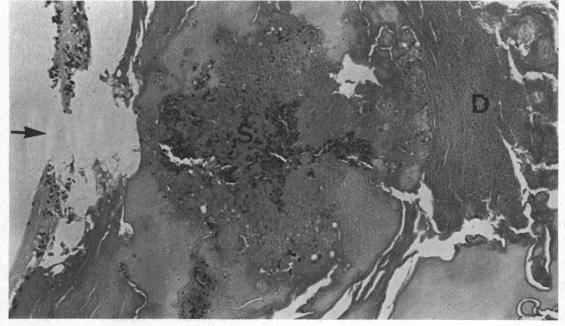

Encephalitozoonosis (nosematosis) causing bilateral cataract in a rabbit.

Bilateral cataract due to a microsporidan believed to be Encephalitozoon cuniculi (also called Nosema cuniculi) is described as an incidental finding in a laboratory rabbit. The route of infection and the significance of the findings are discussed. This is apparently the first report of cataract due to this cause.